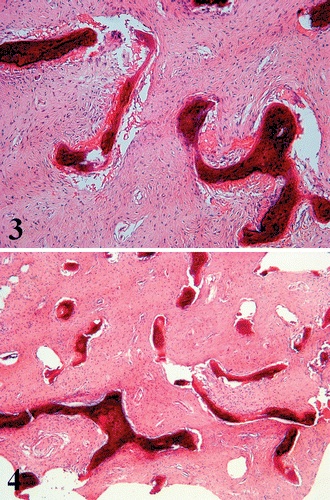

Firm, gritty, pink or white tissue is seen on gross sectioning. [4][2]. Histologically, dysplastic bone has a classic appearance of dense fibrous stroma of low to moderate cellularity surrounding irregularly shaped bony trabeculae. This pattern has been described as resembling “Chinese characters.” (Figure 3) [6][4] No osteoblastic rimming of trabeculae is seen, which is of note in distinguishing fibrous dysplasia from other malignant entities, such as ossifying fibroma. [4][6][1] The surrounding stroma may contain aneurysmal bone cysts, cartilaginous nodules, and myxomatous areas. [4]

Figure 3. Dense fibrous stroma with irregular bony trabeculae. Courtesy of Riddle et al.